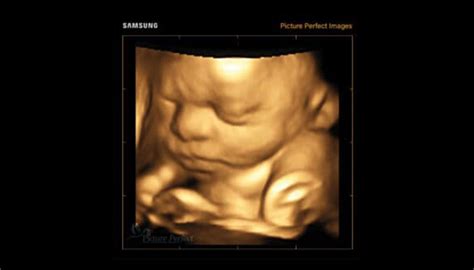

Prima consultatie prenatala este esentiala pentru identificarea factorilor de risc, ce pot afecta mama si / sau fatul. Este consultatia in care se diagnosticheaza sarcina. Medicul va va recomanda setul de analize corespunzatoare primului trimestru - analize de sange si urina, completate de cele ginecologice. Pentru a stabili localizarea sarcinii, varsta gestationala si viabilitatea produsului de conceptie, se va efectua o prima examinare ecografica.

Prima consultatie prenatala este esentiala pentru identificarea factorilor de risc, ce pot afecta mama si / sau fatul. Este consultatia in care se diagnosticheaza sarcina. In cadrul acestui prim consult se va efectua si examenul clinic general (masurarea greutatii, inaltimii, tensiunii arteriale si frecventa pulsului arterial) si cel obstetrical. Medicul va va recomanda setul de analize corespunzatoare primului trimestru - analize de sange si urina, completate de cele ginecologice. Pentru a stabili localizarea sarcinii, varsta gestationala si viabilitatea produsului de conceptie, se va efectua o prima examinare ecografica.

- Săptămânile 6 - 11: Abordarea mai fidelă este prin examinare transvaginală și are rolul de a confirma prezența sarcinii, localizarea acesteia, evaluarea implantării trofoblastice și stabilirea numărului de embrioni și a viabilității acestora.

- Săptămânile 11 - 13 și 6 zile: Se recomandă ecografia la jumătatea săptămânii 12, când fătul oferă o poziție favorabilă atât pentru examinarea transvaginală, cât și transabdominală. Ecografia are rolul de a depista: semnele secundare pentru anomalii cromozomiale; anomaliile structurale majore (defecte ale sistemului nervos central, defecte cardiace majore, defecte de perete abdominal, defecte de tract urinar, defecte scheletice); evaluarea riscului disgravidiei de ultim trimestru (preeclampsie, diabet gestațional, naștere prematură).

Săptămânile 19 - 23: Atunci când dezvoltarea fetală se consideră încheiată, ecografia apreciază morfologia fetală în detaliu, stabilește cu acuratețe localizarea placentară și reevaluează caracteristicile circulatorii prin interogare Doppler. Măsurarea colului uterin se va face corect prin examinare transvaginală. Ca metodă suplimentară de diagnostic prenatal, în prezența unor anomalii fetale, examinarea ecografică poate fi completată cu examinarea prin RMN.

Săptămânile 30 - 32: Examinarea ecografică evaluează ritmul de creștere fetală, aspectul placentei și cantitatea de lichid amniotic, fluxurile Doppler cerebrale și ombilicale fetale, dar și cele uterine materne și, nu în ultimul rând, anomaliile cu apariție tardivă în sarcină.

Săptămânile 36 - 38: Prin intermediul examinării ecografice se apreciază greutatea fătului la naștere, cantitatea de lichid amniotic și aspectul placentei.